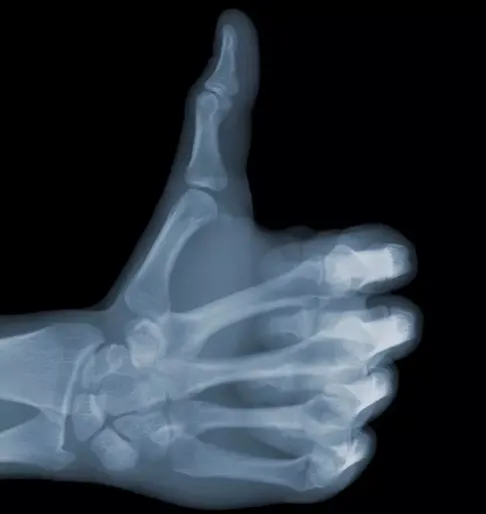

五、X线已经融入人类的生活

(1942年,医护人员给一名婴儿做X线检查。上个世纪起,人类从很小就开始接触X线)

(自幼开始的熏陶,甚至已经让X线成为人们健康理念的一部分)

(1956年的选美比赛中,选手们甚至拍摄了X线,以展示她们标准的身材。这是获胜者和她们的X线片)

(一个多世纪以来,X线早已经超越了医学的范畴,融入人类的文化,成为思想、成为隐喻、成为表达...)